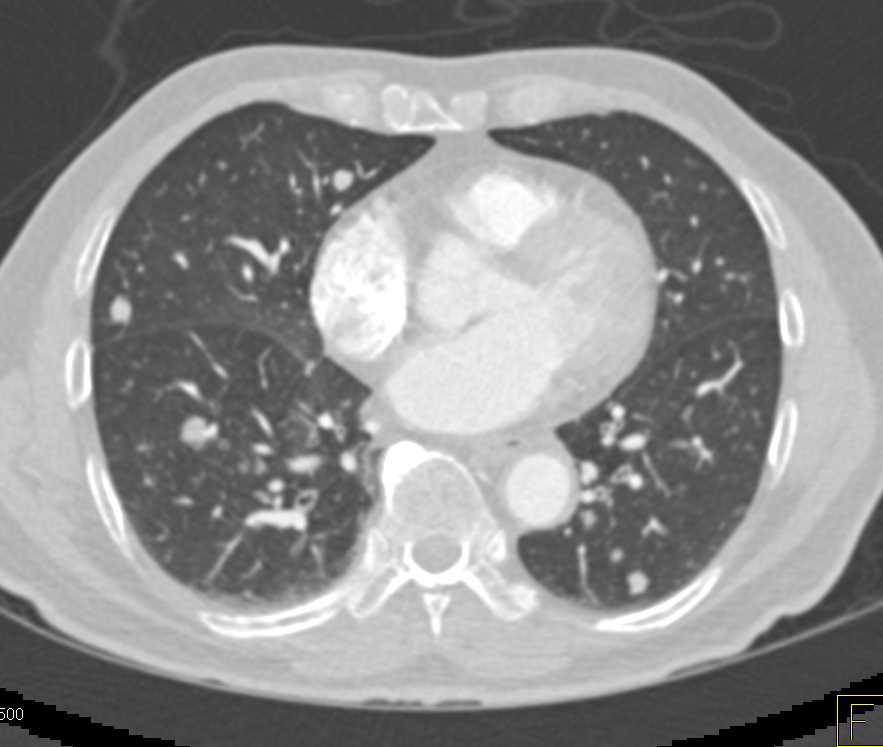

Lymphoma with Adrenal and Liver and Lung Involvement